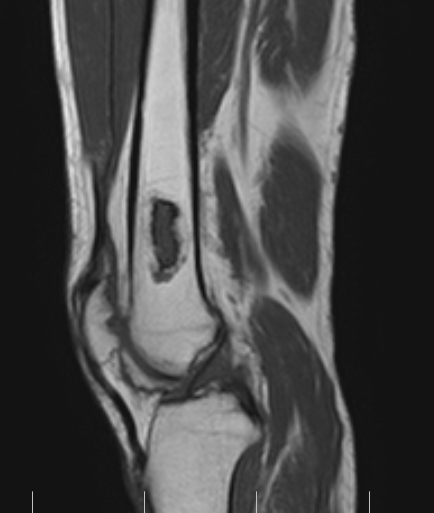

МРТ-информация об инфаркте костного мозга большеберцовой кости

Раздел: Снимки мастерства